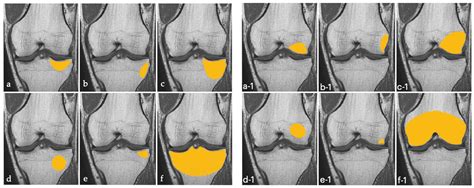

Magnetic Resonance Imaging (MRI) Offers detailed images of the bone marrow and surrounding tissues, making it the gold standard for diagnosing bone marrow edema.